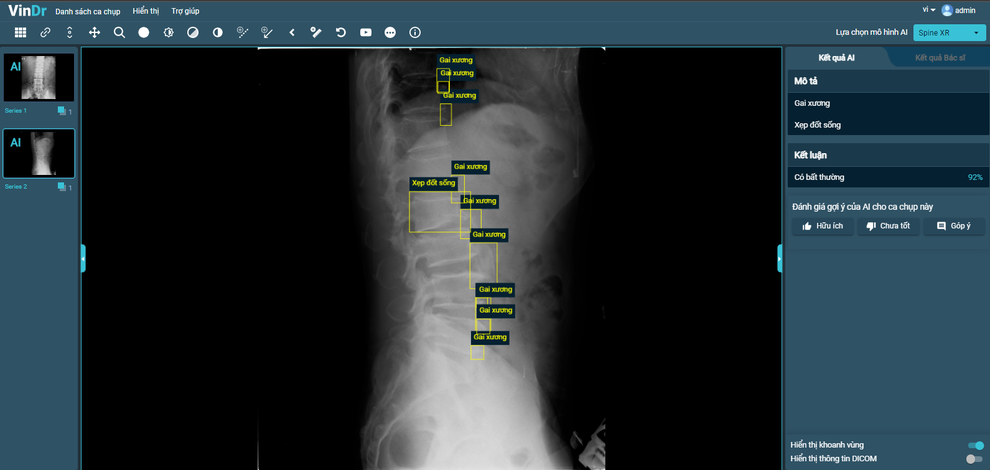

Sau hơn một năm tiếp tục nghiên cứu và phát triển, VinBigdata đã tiếp tục phát triển thành công tính năng chẩn đoán X-quang cột sống, phát hiện 6 loại tổn thương phổ biến tại Việt Nam, bao gồm: gai xương; hẹp khe đĩa đệm; vật liệu phẫu thuật; hẹp lỗ tiếp hợp; trượt đốt sống và xẹp đốt sống với độ chính xác khoảng 90%.

VinDr hoàn thiện tính năng mới SpineXR, hỗ trợ chẩn đoán ảnh X-quang cột sống với độ chính xác khoảng 90%.

(Dân trí) - Chỉ mất vài giây cho mỗi ca chụp, VinDr đã cho kết quả với độ chính xác trung bình trên 90% trong việc chẩn đoán, phát hiện và khoanh vùng đa dạng tổn thương trên phổi, gan, vú và mới đây nhất là cột sống.